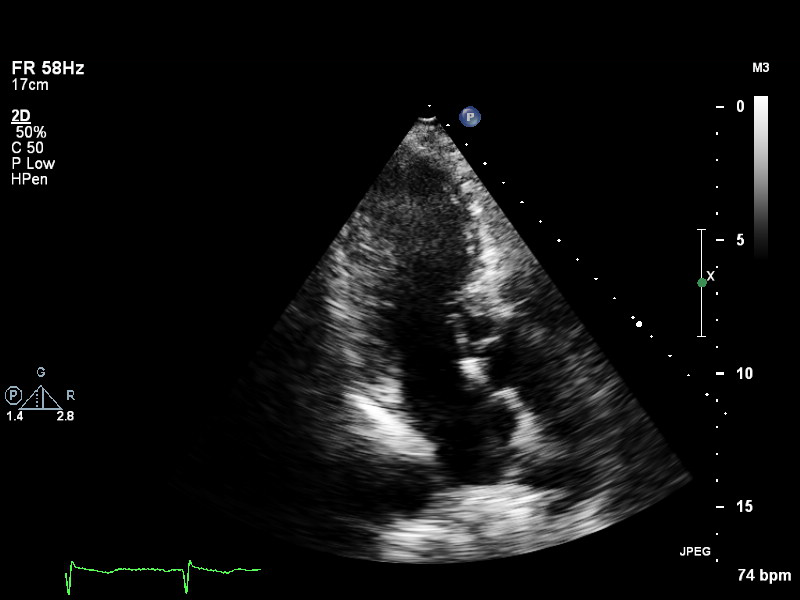

ImageView NameDescription

a4ch-full a4ch-full Apical 4-chamber showing the full depth of all four chambers (no LV/RV focus)

a4ch-ias a4ch-ias Apical 4-chamber, focused on the inter-atrial septum

a4ch-la a4ch-la A4CH with Doppler near MV/LA or 2D covering full LA, not full LV

a4ch-lv a4ch-lv A4CH covering the whole depth of the LV, not the whole depth of the LA

a4ch-ra a4ch-ra Apical 4-chamber focused on the right atrium, or colour Doppler on TV/RA

a4ch-rv a4ch-rv Apical 4-chamber focused on the right ventricle